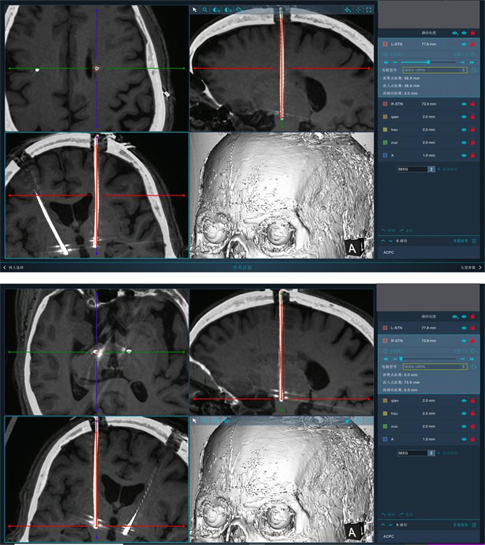

手术过程十分顺利,术后复查头颅CT确定电极置入与计划靶点位置一致,手术成功!

刘岳主任说:“DBS手术步骤繁多,对精准度要求极高,差之毫厘,失之千里,我们中心常规是用立体定向头架来完成DBS手术,本次引进了手术机器人辅助,从手术后的CT影像融合结果看,电极植入靶点和我们术前预计划的路径基本一致,这说明机器人辅助DBS手术精准度非常高,完全可以实现在手术中不带头架,通过机器人的机械臂打靶校准误差,将误差控制在0.3mm以下,可以大大缩短手术时间,简化手术流程,减少患者在术中感染风险,降低术后并发症的发生。”